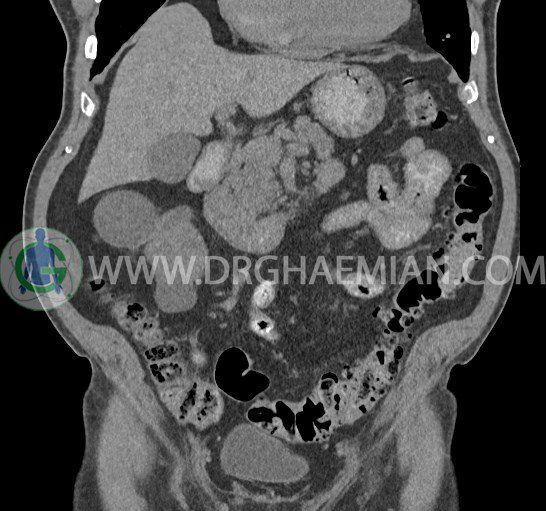

سی تی اسکن لگن یکی از روش های تصویربرداری با سی تی اسکن است. این روش با استفاده از تشعشعات تصاویر عرضی از ناحیه شکمی ایجاد میکند. در این کیس ديورتيكولوزيس، کیست های کورتیکال در هر دو کلیه، لنفادنوپاتی، کلسیفیکاسیون دیواره آئورت و شریان ایلیاک، تغییرات DJD ناحیه توراکولومبار و پروستات بزرگتر از عادی دیده می شود.

در سي تي اسکن اسپيرال شکم و لگن با و بدون کنتراست خوراکی و وريدی (مولتي ديدکتور 16 با مقاطع ظريف و بازسازي هاي ساژيتال و کرونال):

– کيست هاي کورتيکال ساده به قطر 5 mm تا 50 mm در کليه راست و به قطر 5mm تا 55 mm در کليه چپ

– توده ايزودنس به ابعاد mm 17 x 28 در پره ائورت مجاور قسمت تحتاني D3 دئودنوم مطرح کننده لنفادنوپاتي و با احتمال کمتر آنوريسم ترومبوزه (نيازمند مطابقت سونولوژيک)

– کلسيفيکاسيون ديواره آئورت و شريان ها ايلياک همراه با نشانه هاي ترومبوز مورال در بيفورکاسيون ائورت با امتداد به پروگزيمال هاي شريان هاي ايلياک

– ديورتيكولوزيس در کولون نزولي وسيگموئيد

لنفادنوپاتي به ابعاد mm 22 x 25 مجاور شريان ايلياک خارجي چپ و به ابعاد mm 17 x 28 مجاور شريان ايلياک خارجي راست

– تغييرات DJD در ناحيه توراکولومبار و

– پروستات به ابعاد mm 45 x 54، بزرگ تر از نرمال

مشهود است.